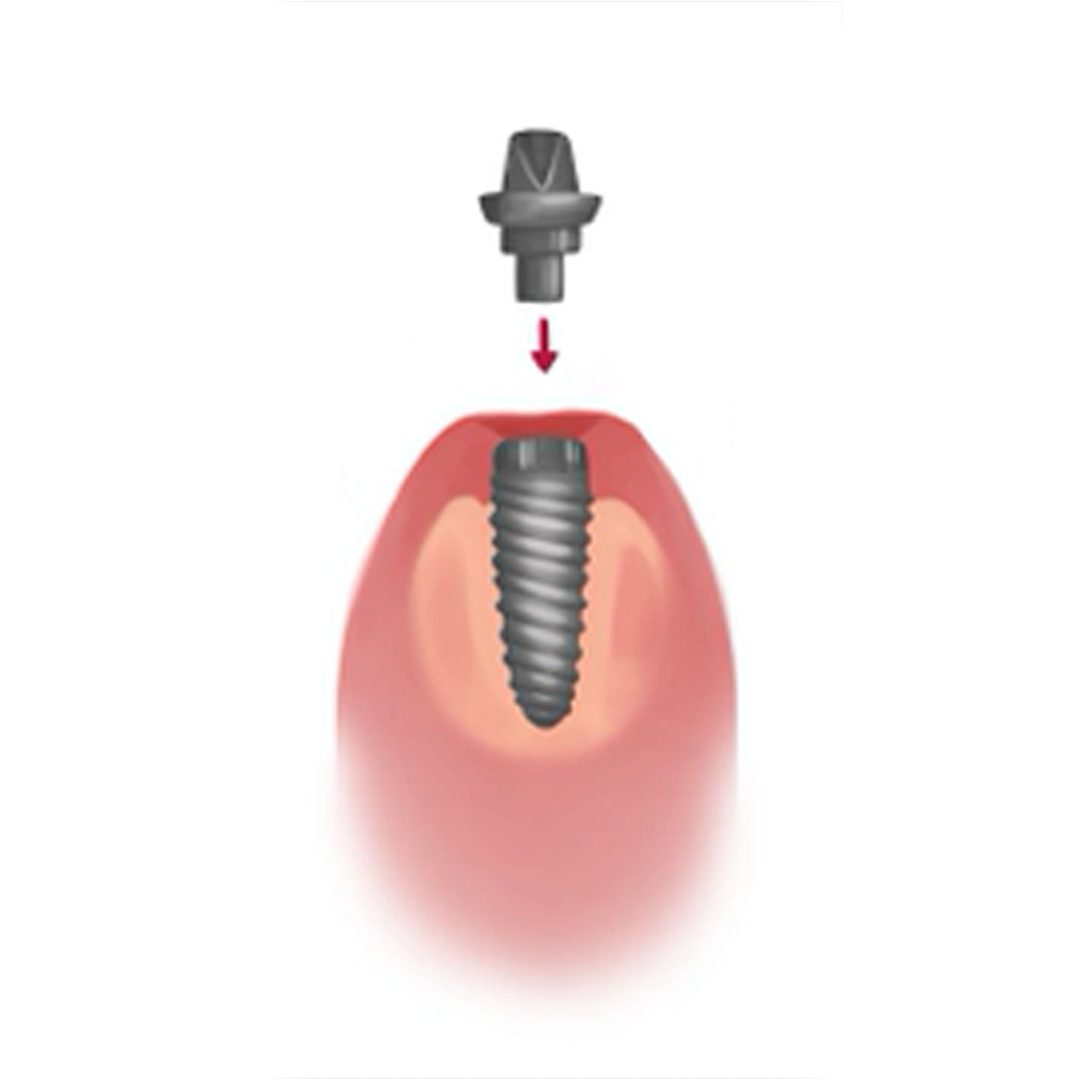

Core Stages of Implant Surgery

The entire dental implanting process can generally be broken down into four core stages, spanning over the course of 4 – 6 months in total. The four stages are; implant fixture placement, healing & osseointegration, abutment placement and the placement of the final dental prosthesis.

For the majority of patients, these 4 core stages are not carried out in a single dental visit or surgery. The recovery time of 4 – 6 months post-surgery allows the implant fixtures to heal and permanently fuse with the surrounding jaw bone (Stage 2: Osseointegration).

The long term success of any dental implant is highly reliant on the osseointegration of the implant with the surrounding bone. Failure to osseointegrate will result in the failure of the dental implant.

Once the dental implant fixture has adequately osseointegrated with the jaw bone, the abutment and prosthesis can be attached to the implant fixture, completing the entire dental implant process.

3. Affix Abutment

The gum is reopened to expose the implant fixture in order to attach the abutment.